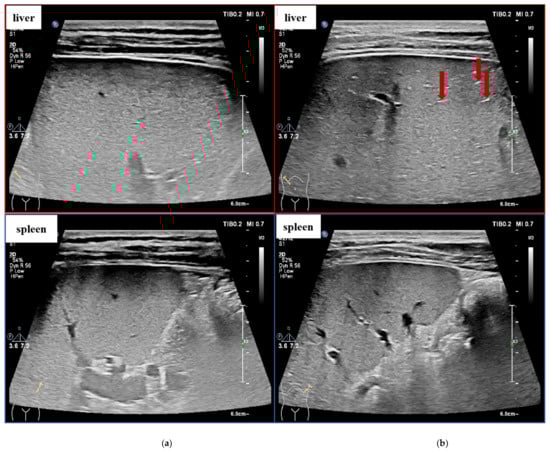

Figure 2 shows some example cases in our dataset. Liver images with different LF stages show possible US image signs, and it is more obvious to see the changes in the liver parenchyma when comparing them with the spleen US images from the same patient. In this study, we proposed a two-stage Siamese network to analyze the correlation between the stage of fibrosis and the liver–spleen differences (LSDs) and combined the LSDs for LF staging to improve the performance of automated LF staging models.

Figure 2.

US image signs of fibrotic liver and spleen (S1–S4 means liver fibrosis stages 1–4, which are determined through liver biopsy by pathologists. The red arrows pointing to US signs of fibrosis as examples). (a) S1: Rough echo of liver parenchyma. (b) S2: “strip pattern” liver fibrosis. (c) S3: significantly rough echo of liver parenchyma with uneven distribution. (d) S4: hyperplasia nodules of liver parenchyma.